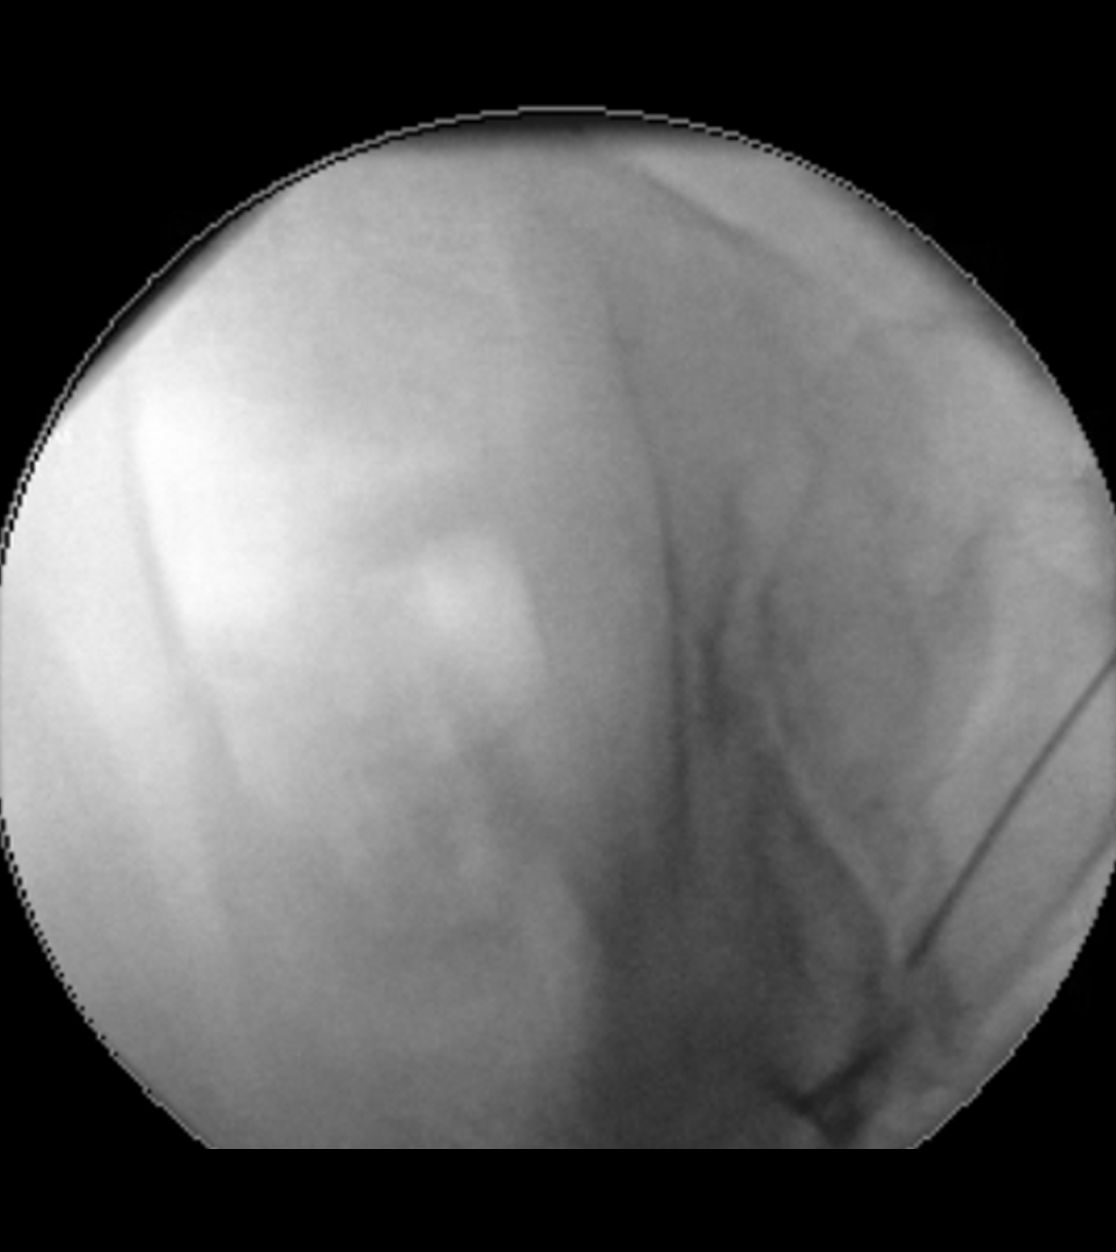

Am Bauch implantierte Medikamentenpumpe (Pfeil)